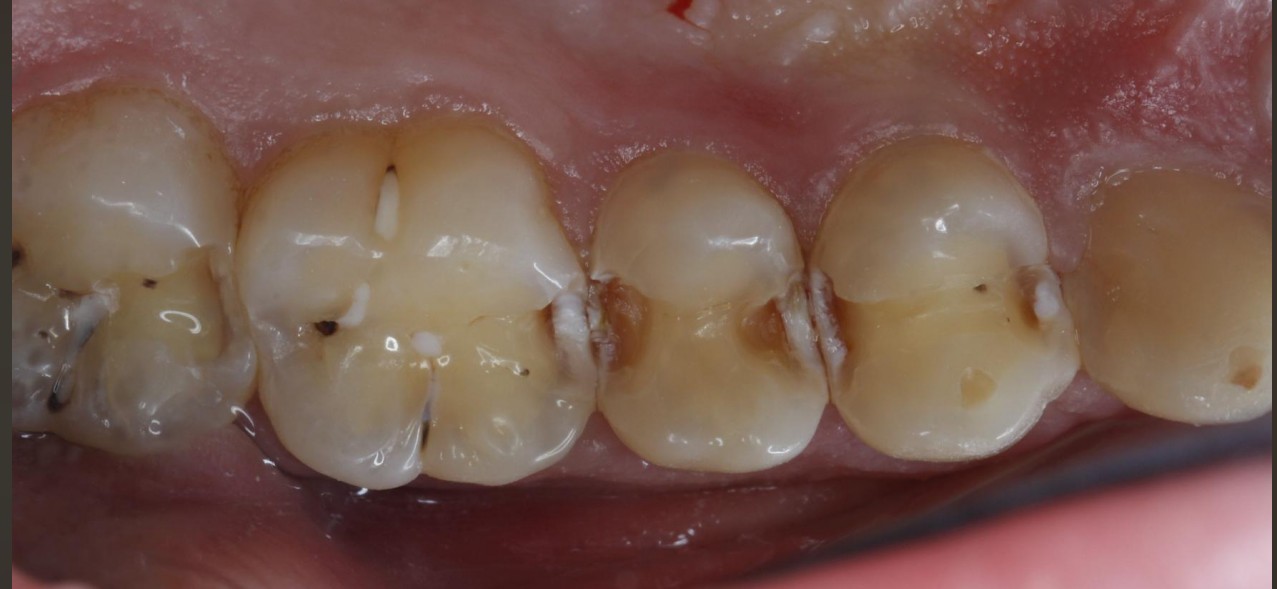

门诊经常遇到常年把碳酸饮料当水喝的患者,严重损伤了牙齿的健康,检查发现牙齿脱矿.龋坏特别严重,特别是邻面龋坏,治疗也非常麻烦,很多情况下,简单的补牙都解决不了长久性问题,想要经久耐用,可以选择嵌体,高嵌体,全瓷牙冠修复,更重要是杜绝不良嗜好;有图有真相!我们采用德国西诺德瓷睿刻即刻修复系统,等待1小时,完成当日修复。